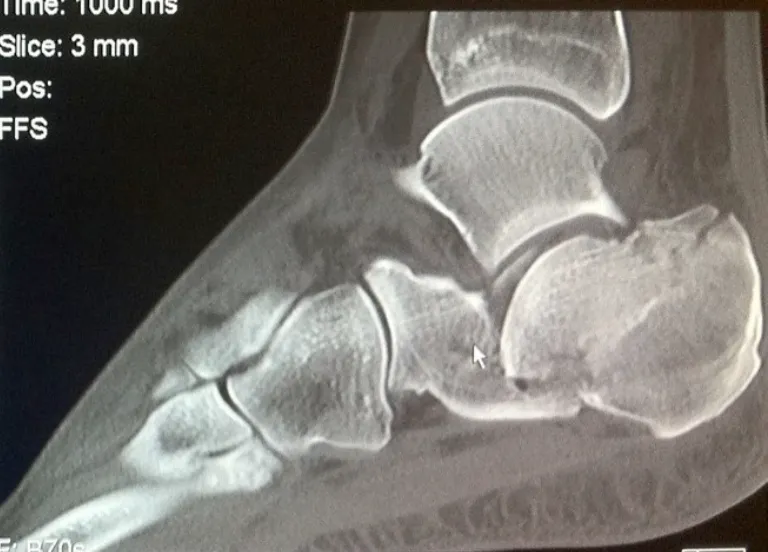

A CT scan is essential to accurately evaluate:

- The degree of articular involvement

- The number of fracture fragments

- Joint displacement

- Overall fracture morphology

The CT will identify the severity of the injury and whether surgery is indicated or not.

Severity is determined on the CT by:

- The degree of joint displacement

- Sanders classification on CT